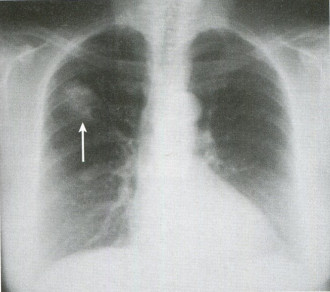

3일간 약을 복용한 후 기침은 어느 정도 완화되었으나 여전히 오른쪽 가슴 통증이 지속되어 드물긴 하지만 기침 시 갈비뼈 골절이 유발될 수 있어 갈비뼈 X선을 촬영하였습니다.

갈비뼈 X선에서는 골절 등 이상 소견이 없었으나 흉통이 호전되지 않고 지속되고 있으며 X선에서는 잘 확인되지 않는 미세 골절 여부를 확인하기 위해 갈비뼈 초음파를 실시하였습니다.

▶ 진단 흉부 엑스레이 – 가장 기본적으로 할 수 있는 검사 방법, 미세 골절의 경우 엑스레이로 확인하기 어려운 초음파 검사 – 엑스레이 검사상 골절 소견이 관찰되지 않을 경우 갈비뼈 골절 진단에 사용 가능.미세 골절 확인 및 주변 장기 손상을 확인할 수 있다는 장점이 있다.뼈 주사 검사, 흉부 CT-X선 검사상 확인되지 않은 골절 감별로 사용 가능.